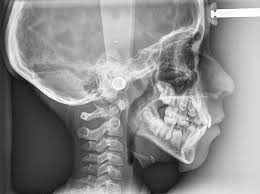

RX maxilar

Es la especialidad médico-quirúrgica que ocupa la prevención, estudio, diagnóstico y tratamiento de la patología de la boca y cara, así como de las estructuras del cuello relacionadas con las mismas.

Los equipos de Cirujanos Maxilofaciales en las clínicas y hospitales de Barcelona, ofrecen un trato individualizado y de alto nivel tecnológico a los pacientes y  se dedican al estudio, prevención, diagnóstico, tratamiento y rehabilitación de las Enfermedades Congénitas y Adquiridas del Cráneo, Cara, Cabeza y Cuello, Cavidad Oral y Maxilares (incluyendo la Dentición). Por ejemplo, Tumores de Glándula Parótida, Abcesos Amigdalares y Base de Lengua, Fracturas de Mandíbula y Cirugía Cordales. Realizan intervenciones desde la cirugía estética del esqueleto facial hasta la reposición de dientes ausentes mediante implantes osteointegrados con la tecnología más avanzada.